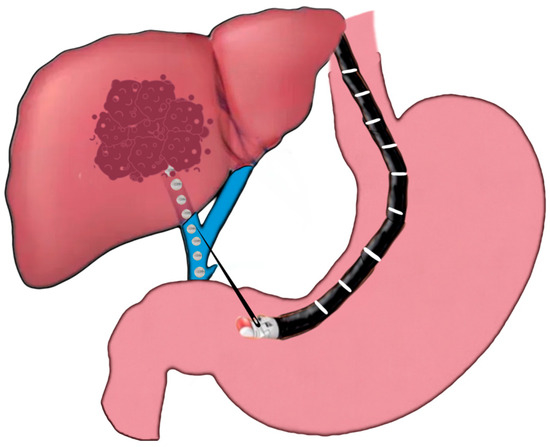

2.3.2. EUS-Guided Intrahepatic Portosystemic Shunt Placement

- Buscaglia, J.M.; Dray, X.; Shin, E.J.; Magno, P.; Chmura, K.M.; Surti, V.C.; Dillon, T.E.; Ducharme, R.W.; Donatelli, G.; Thuluvath, P.J.; et al. A new alternative for a transjugular intrahepatic portosystemic shunt: EUS-guided creation of an intrahepatic portosystemic shunt (with video). Gastrointest. Endosc. 2009, 69, 941–947. [Google Scholar] [CrossRef] [PubMed]

- Binmoeller, K.F.; Shah, J.N. Sa1428 EUS-Guided Transgastric Intrahepatic Portosystemic Shunt Using the Axios Stent. Gastrointest. Endosc. 2011, 73, AB167. [Google Scholar] [CrossRef]

- Schulman, A.R.; Ryou, M.; Aihara, H.; Abidi, W.; Chiang, A.; Jirapinyo, P.; Sakr, A.; Ajeje, E.; Ryan, M.B.; Thompson, C.C. EUS-guided intrahepatic portosystemic shunt with direct portal pressure measurements: A novel alternative to transjugular intrahepatic portosystemic shunting. Gastrointest. Endosc. 2017, 85, 243–247. [Google Scholar] [CrossRef] [PubMed]